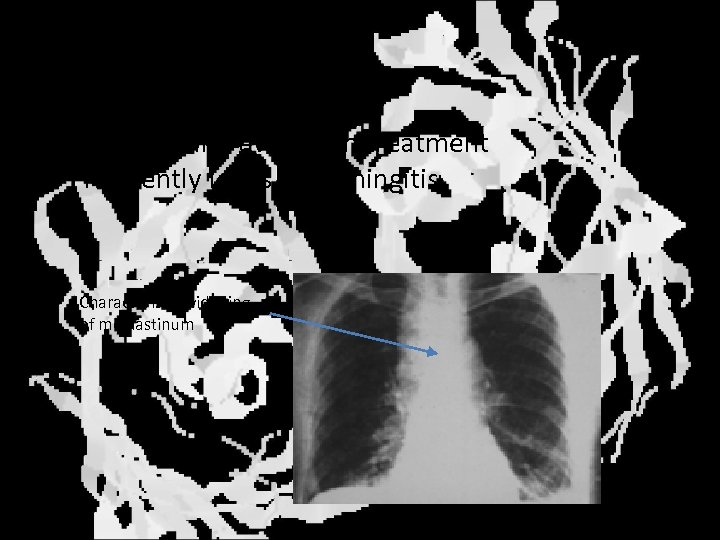

Inhalation anthrax • Inhalation of spores • High lethality even with treatment • Frequently leads to meningitis Characteristic widening of mediastinum